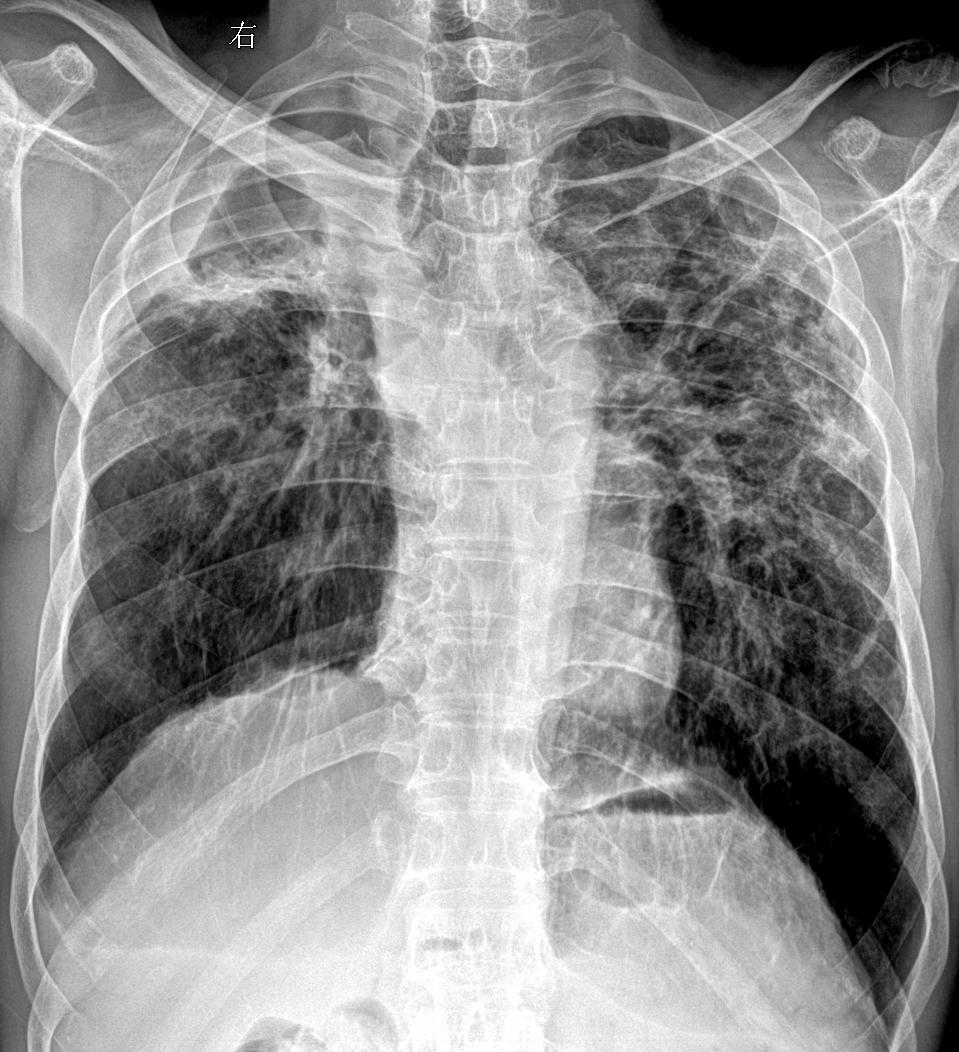

考完了大家考的怎么样 开始继续搬砖吧 男61疫情得过白肺 现在胸闷